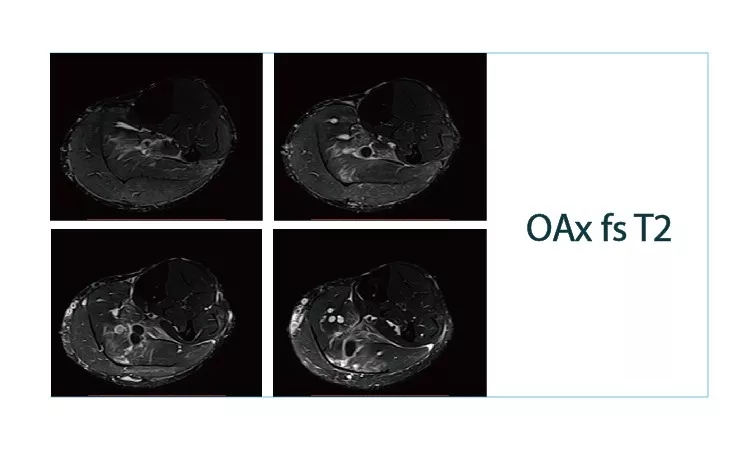

【朗润影像档案】20180615磁共振影像病例结果讨论